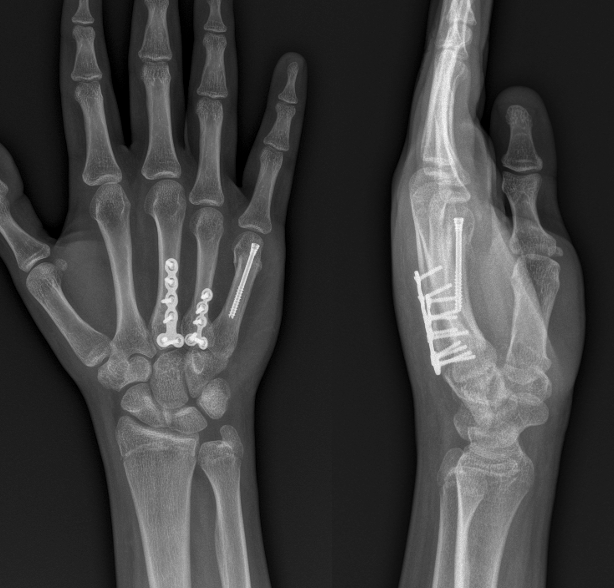

Nos dedicamos a devolver la función y la confianza a tus manos y brazos. Tratamos desde los problemas más frecuentes hasta casos complejos que requieren cirugía avanzada y reconstrucción.